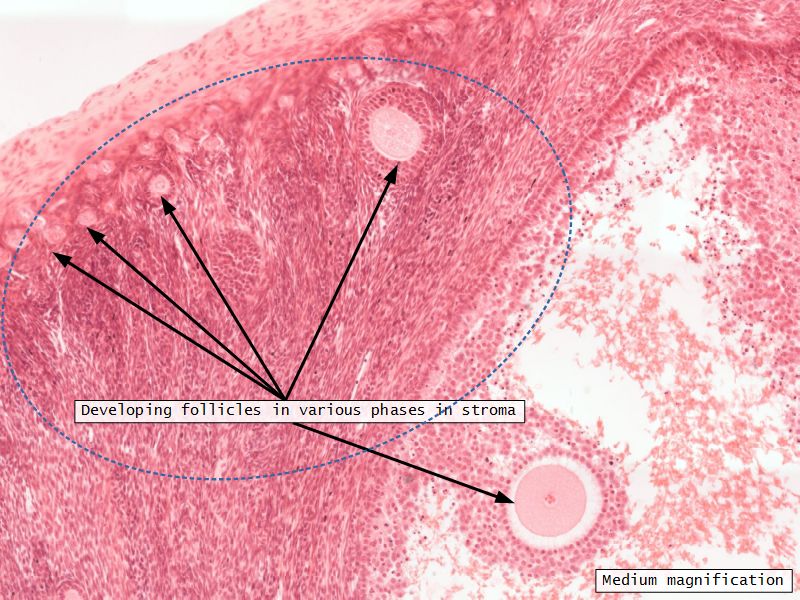

Ovaries

Slide 24

Section of the ovary

1. Outer covering. 1'. Attached border. 2. Central stroma. 3. Peripheral stroma. 4. Bloodvessels. 5. Vesicular follicles in their earliest stage. 6, 7, 8. More advanced follicles. 9. An almost mature follicle. 9'. Follicle from which the ovum has escaped. 10. Corpus luteum.

Ovary

- Capsule covered by modification of peritoneum

- Called germinal epithelium

- Simple squamous/cuboidal

- Subdivided

- Not clearly defined

- Cortex - contains ovarian follicles

- Medulla - vascular

Cortex

- Tunica albuginea

- Irregular dense CT capsule

- Follicles in various phases

- Stroma containing follicles

Stroma

- Highly cellular loose CT

- Fibroblasts

- Elastic & collagen fibres

- Form layers around follicles

Medulla

- Blood vessels

- Hilus cells

- Stroma